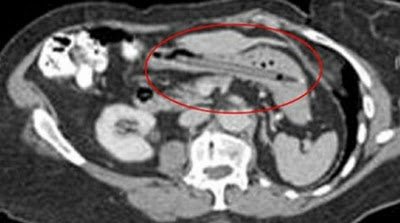

Μπορεί να ακούγεται απίστευτο και όμως είναι πραγματικότητα! Ύστερα από μια εξέταση που έκανε, οι γιατροί διαπίστωσαν ότι υπήρχε στο παχύ έντερό της ένα μακρύ αντικείμενο, το οποίο της δημιούργησε φλεγμονή. Όταν ρωτήθηκε τι είχε συμβεί, εκείνη απάντησε ότι είχε χρησιμοποιήσει το στυλό για να σπρώξει τις αμυγδαλές της και εκείνο γλίστρησε! Φυσικά αμέσως υποβλήθηκε σε χειρουργείο να την αφαίρεση του στυλό από την γυναίκα. Το ακόμη πιο απίστευτο σε αυτή την ιστορία είναι ότι το στυλό εξακολουθούσε να …γράφει!